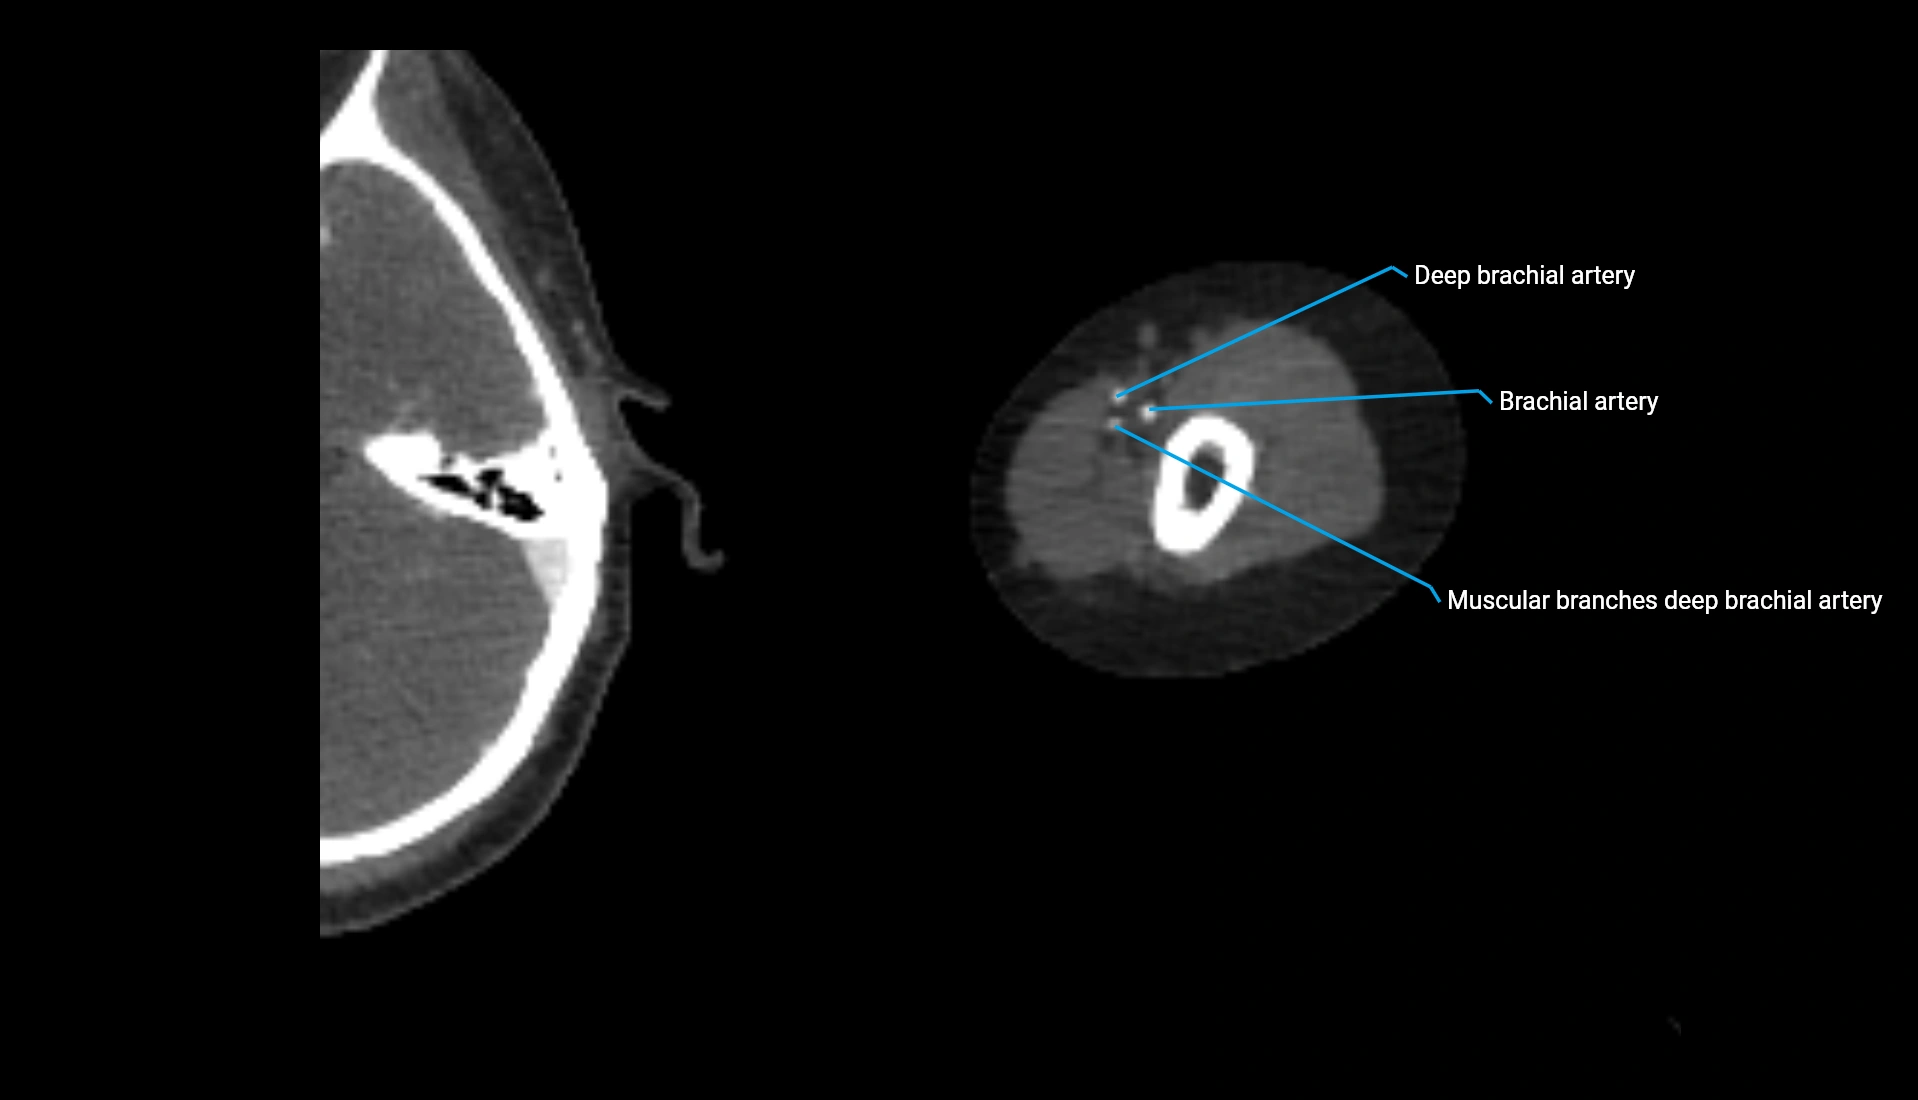

CT Appearance

Non-Contrast CT:

• Cortex: High-density, sharply defined

• Subchondral bone: Dense cancellous matrix

• Articular surface: Smooth concave contour articulating with the capitellum

• Excellent for evaluating bone integrity, alignment, and subtle fractures